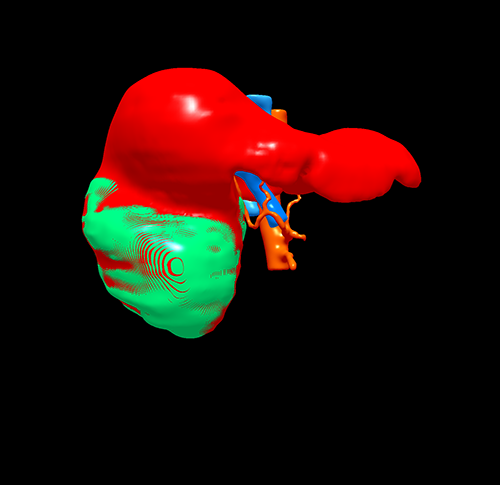

右肝巨大肝癌---右半肝切除